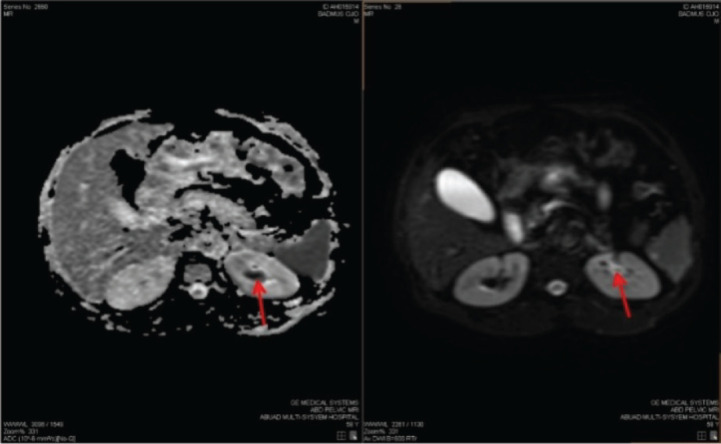

Upper urinary tract urothelial carcinomas (UTUCs) are rare malignant neoplasms, representing about 5% of all urothelial carcinomas (UCs). The incidence of primary UTUC in the renal pelvis and calyx is quite rare. UTUC is a high-grade tumour with a poor prognosis at presentation. Characteristically, UTUC presents with symptoms such as gross and microscopic hematuria or flank pain. Its mode of definitive diagnosis remains histopathology examination, despite using computed tomography urography (CTU) as the gold imaging standard. However, atypical clinical presentations and abnormal radiologic findings could lead to misdiagnosis of UTUC. We report a 59-year-old male who presented with recurrent left flank pain of 2 years duration, and an episode of hematuria. A CTU showed no classic radiologic feature of upper UCs; however, his abdominal magnetic resonance imaging was suggestive. He subsequently had a left radical nephroureterectomy. The post-operative histology report showed a primary invasive high-grade UC of the left renal pelvis and calyx. He was counseled on the findings and placed on surveillance. There are few reported cases of UTUC of the renal pelvis and renal calyx; given that it is a rare malignancy. This is quite concerning, especially with the missed imaging finding by CTU.